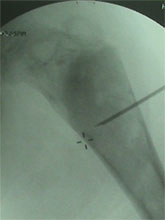

Any acute, and unstable SCFE requires emergent treatment. Stable slips also need to pinned on an elective basis. Untreated or unreduced SCFE can lead to Avascular Necrosis of the epiphysis, chondrolysis and Femoral-Acetabular impingment leading to early hip arthritis. Severe Slip may required open reduction using the Anterior or Watson-Jones Approach or the Safe-Surgical Hip (GANZ) Dislocation approach.

SCFE treated with the Ganz Approach